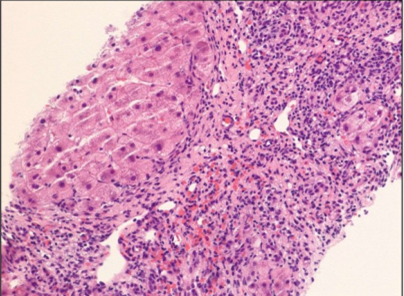

A 58-year-old Hispanic female with a past medical history of prediabetes is referred to you for evaluation of elevated liver enzymes. Her most recent labs included ALT 110 (U/L), AST 89 U/L, ALP 169 U/L, and total bilirubin 0.8 (her MELD 3.0 was 8). She did not drink alcohol or take medications associated with DILI, and hepatitis B and C serologies were negative. Autoimmune serologies were notable for a positive anti-smooth muscle antibody (1:40), with negative anti-nuclear antibody, anti-mitochondrial antibody, anti LKM, and soluble liver antigen. Total IgG was 1093 mg/dL. Abdominal imaging was consistent with cirrhosis. Percutaneous liver biopsy (figure below) showed a dense mononuclear portal infiltrate (plasma cell-rich) with extensive interface and lobular hepatitis and widespread confluent necrosis (bridging parenchymal collapse) and portal fibrosis with focal architectural distortion (Batts- Ludwig Stage 3/4), suggestive of autoimmune hepatitis.

Liver biopsy:

A repeat liver biopsy was obtained to evaluate the response to therapy as the patient exhibited a delayed and atypical response. This showed a significant improvement in the degree of interface hepatitis and an improvement in necroinflammation and lymphocytic infiltration. There continues to be bridging fibrosis and focal regenerative nodule formation (Batts-Ludwig Stage 4/4)